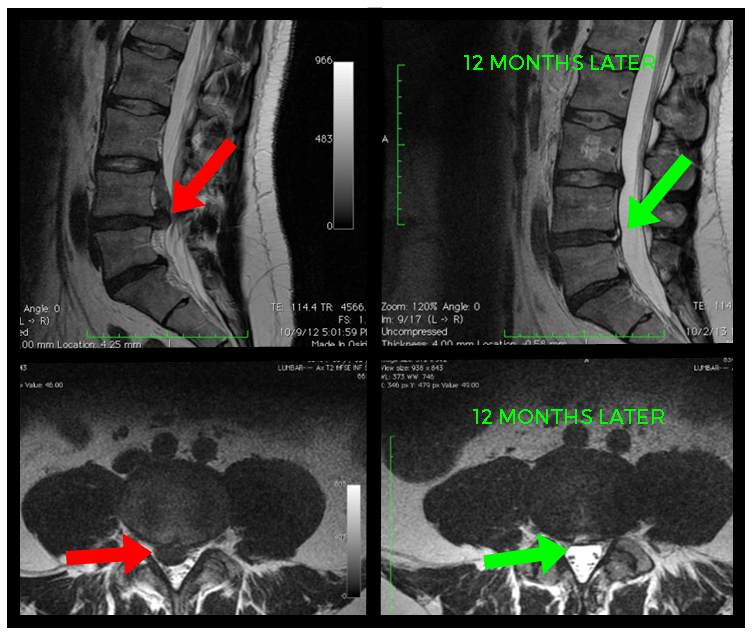

From www.wjgnet.com

Resorption of upwardly displaced lumbar disk herniation after Herniated Disc In Back Recovery Time The ultimate guide to recovery. The good news is that in most cases — 90% of the time — pain caused by a herniated disc will go away on its own within six months. While every individual is different, here is a general timeline for when to expect to get back to regular activity and exercise following. Signs a herniated. Herniated Disc In Back Recovery Time.